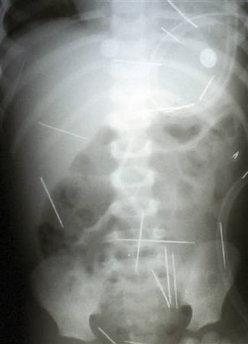

Wino Posted December 23, 2009 Author Report Posted December 23, 2009 Dozens of needles are seen in this undated X-ray handout taken of a two-year-old boy in Salvador. A Brazilian toddler is making a good recovery after surgery to remove the first of 31 sewing needles pushed into his body by his stepfather in a cruel act that has enraged locals. reuters